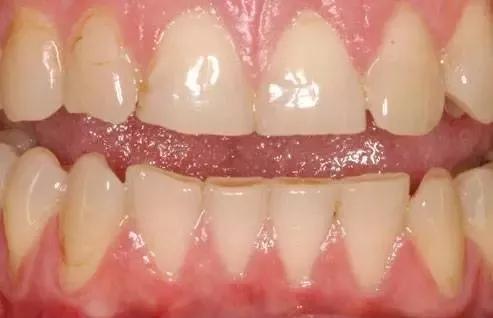

一些全身健康问题也会影响牙釉质。这张图中显示了暴食症患者的牙齿,由于常常呕吐,胃酸反流入口腔导致牙釉质被侵蚀。另外,胃食管返流综合症也会引起牙釉质的损坏。